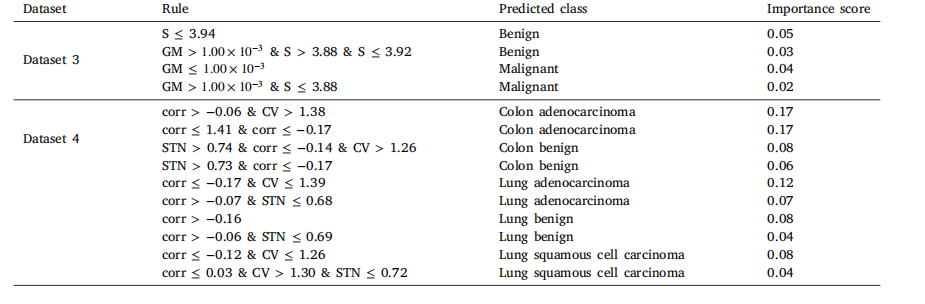

Table 12Decision tree rules for top two datasets based on classification performance.

表12 基于分类性能的前两个数据集的决策树规则。

Table 13RuleFit rules for top two datasets based on classification performance.

表13 基于分类性能的前两个数据集的RuleFit规则。